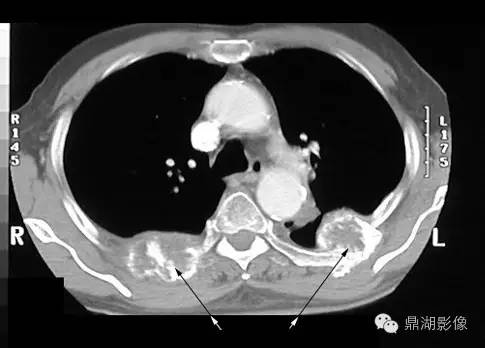

肺癌转移

X线片表现:好发于肋骨、脊柱、骨盆及颅骨,其次为肱骨、股骨,也有转移至胫、腓、尺、桡及足骨者;破坏灶单发或多发,大多为溶骨性破坏,边缘模糊,骨皮质常有破坏,有时肋骨、坐骨及长骨受累,骨干可完全被破坏吸收而不留痕迹;肺癌成骨性转移很少见,表现为斑点状或絮状密度增高影,密度由毛玻璃状高至象牙质样。部分病例出现软组织肿块,一般无骨膜反应。

(四)肺癌骨转移 肺癌骨转移的发生率意见不一,Abrams报道发生率32.5%,占第四位。国内文献报道发生率6.7%(1964年)~45.6%(1987年),呈逐年增加趋势。肺癌骨转移女性多发,年龄多在50岁以上。